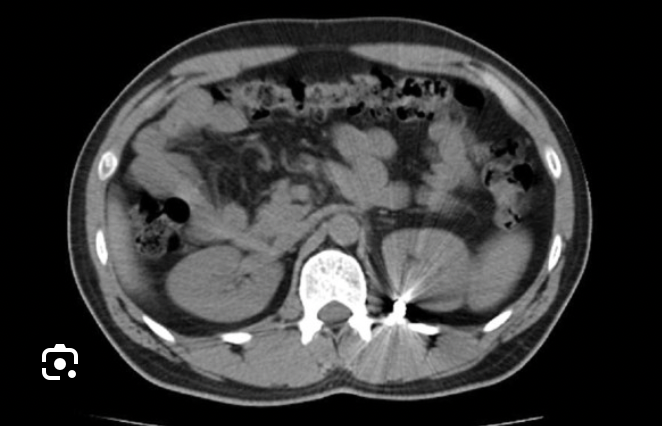

transverse

Which CT view?

Acute appendicitis

CT Abdomen/Pelvis IV contrast

Diverticulitis

CT Abdomen/Pelvis IV contrast

Intra-abdominal abscess

CT Abdomen/Pelvis IV contrast

Pyelonephritis

CT Abdomen/Pelvis IV contrast